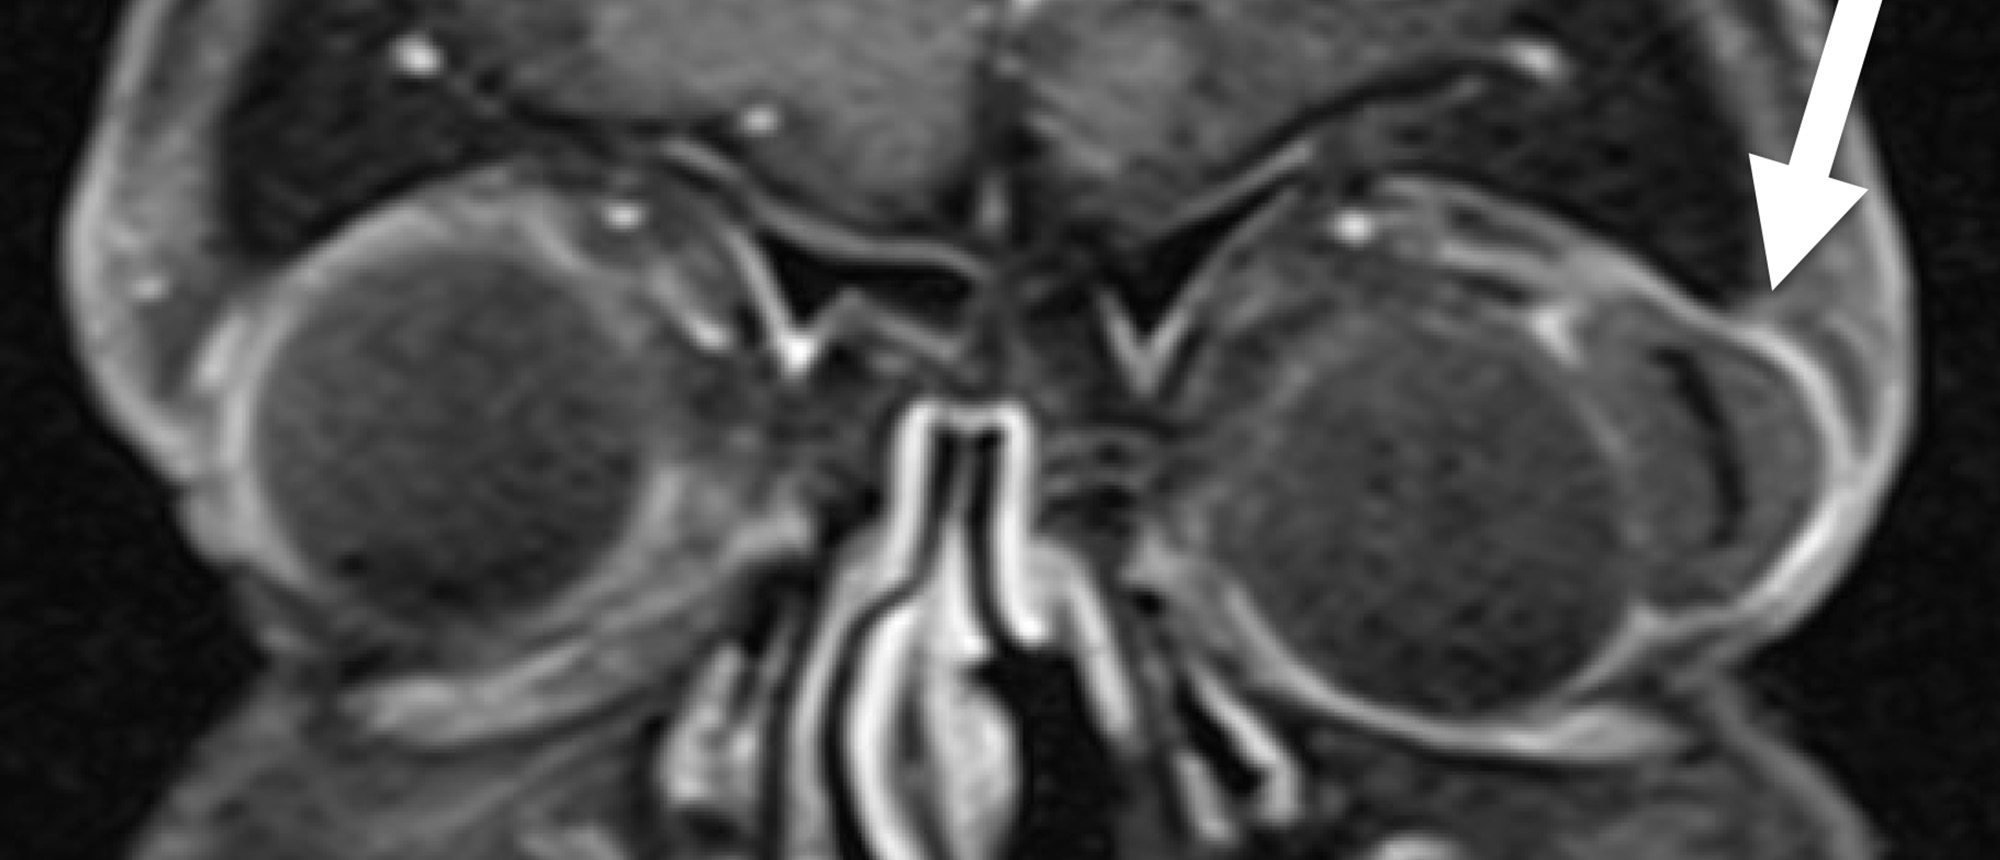

Acute Myeloid Leukemia

Specialty: Glaucoma

Include in Catalogue?: No

Presenter(s): Caroline M. Borie, MD

Faculty Discussant(s): Chris R. Alabiad, MD; Sander R. Dubovy, MD

Abstract A previously healthy child presented with bilateral periorbital edema, right greater than left proptosis, with generalized facial swelling and copious nasal discharge, not improved on antibiotics. Imaging revealed multiple extraconal soft tissue masses in the orbits bilaterally with bilate…

Acute Myeloid Leukemia A previously healthy child presented with bilateral periorbital edema, right greater than left proptosis, with generalized facial swelling and copious nasal discharge, not improved on antibiotics. Imaging revealed multiple extraconal soft tissue masses in the orbits bilateral…

Specialty: Ocular Oncology

Type: Online Grand Rounds

Include in Catalogue?: Yes

Presenter/Faculty: Alabiad, Borie, Dubovy